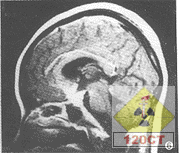

6.CT、MRI檢查

腦CT約半數顯示異常。炎性滲出物充填基底池及腦外側裂,部分患者腦實質內顯示結核瘤,直徑0.5~5cm,單發或多發,多位於額、顳及頂葉。增強掃描顯示環狀強化或密度增高。

腦MR採用Gd-DTPA增強,顯示基底池等部位強化,並較易發現腦實質內的結核瘤和小梗死灶。